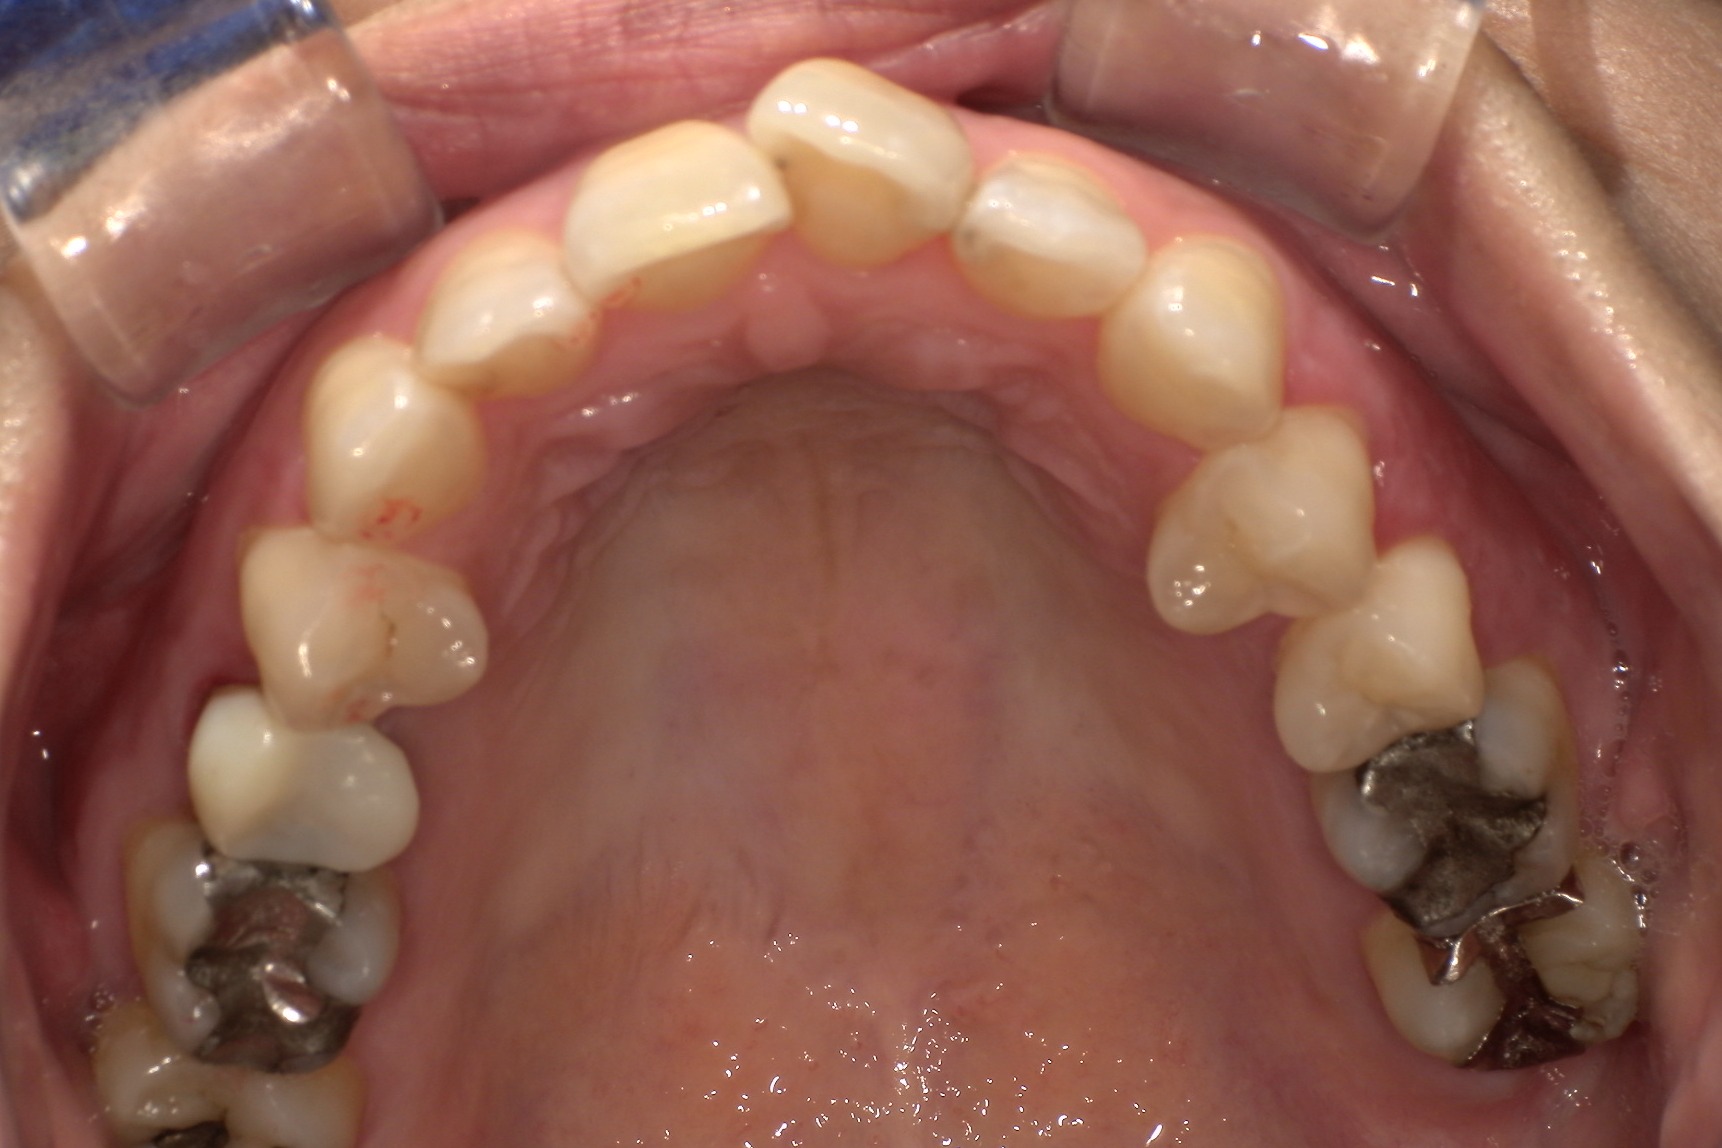

ホワイトニングも同時並行で行い、「毎週自分の歯並びの写真を撮っていたので、綺麗になっていくのが楽しみだった」という矯正体験について45歳主婦のN.T.様にお話を伺いました。

毎週自分で歯並びの写真を撮っていたので日々綺麗になっていく歯並びを見るのが嬉しく、家族からも綺麗になったねと言われました! マウスピース矯正と並行してホワイトニングも行っていたので、歯が格段に綺麗になるのを実感できたのが嬉しかったです。